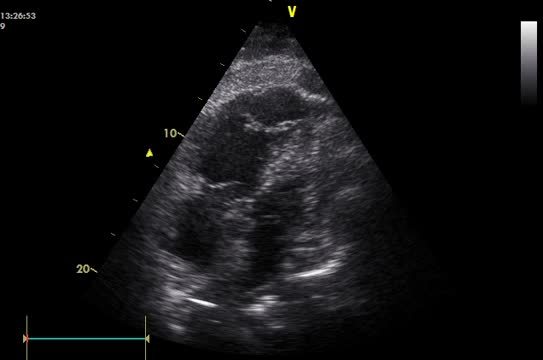

Paciente varón de 53 años que comienza con cuadro de disnea, fiebre y dolor torácico pleurítico, de inicio súbito. A su llegada a urgencias presentaba hipotensión, taquicardia y saturación arterial del 80% respirando aire ambiente. El electrocardiograma mostró taquicardia sinusal con patrón S1Q3T3 con ondas T negativas de V1-V6. Con una alta sospecha de tromboembolismo pulmonar (TEP), se practicó un ecocardiograma portátil (EP) urgente que mostró dilatación y disfunción del ventrículo derecho (VD), con preservación de la contractilidad del ápex (signo de McConnell [SMC]) (fig. 1A-B) y datos indirectos de hipertensión pulmonar severa. Ante la inestabilidad hemodinámica se optó por realizar fibrinólisis con alteplasa (rtPA), con buena respuesta clínica. Tras su estabilización, se realizó angiotomografía de tórax que confirmó la presencia de un TEP bilateral extenso con signos de recanalización incipientes (fig. 1C-D, flechas). Un eco-doppler confirmó la presencia de trombosis venosa profunda femoropoplítea derecha. Fue dado de alta sin complicaciones

A) Ecocardiografía. La imagen de 4 cámaras en sístole muestra acinesia de la pared libre del VD con hipercinesia del ápex (flecha). B) Ecocardiografía. Imagen de 4 cámaras en diástole, dilatación del VD, ápex de VD (flecha). C) Angiotomografía de tórax con contraste, plano axial. Trombos intraluminales en ambas ramas pulmonares con recanalización parcial (flechas). D) Angiotomografía de tórax con contraste, plano coronal. Trombos intraluminales en ambas ramas pulmonares (flechas). VD: ventrículo derecho; VI: ventrículo izquierdo.